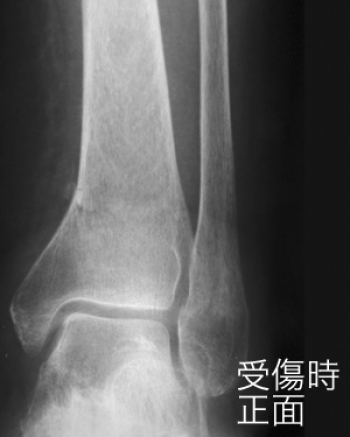

º£Æü¡¢¤´¾Ò²ð¤¹¤ë¤Î¤Ï¡¢²¼Âܱó°ÌüÉô¹üÀޤˤĤ¤¤Æ¤´¾Ò²ð¤·¤Æ¤¤¤­¤Þ¤¹¡£

²¼Âܹü±ó°ÌüÉô¹üÀÞ

­´ØÀáÉô¤Î¹üÀޤϡ¢¤È¤¯¤Ë¥¹¥Ý¡¼¥Ä³°½ý¤Ç¿ȯ¤·¤Þ¤¹¡£

²ò˶³ØÅª¾õÂ֤ؤβóÉü¤Ë¼ºÇÔ¤¹¤ë¤È¡¢Â­´ØÀá¤ÎưÍÉÀ­¤ä¡¢ÊÑ·ÁÀ­´ØÀá¾É¤ò»Ä¤·¡¢µ¡Ç½¾ã³²¤òÀ¸¤º¤ë¤³¤È¤â¤¢¤ë¡£

²¼Âܹü¹ü´´Éô¹üÀÞ¤ÎʬÎà

­¡³°Å¾·¿¹üÀÞ¡ÊPott¹üÀÞ¤Þ¤¿¤ÏDupuytren¹üÀÞ¡Ë

­¢»°²ÌÉô¹üÀÞ¡Ê¥³¥Ã¥È¥ó¹üÀÞ¡Ë

­£Æâž·¿¹üÀÞ

³°Å¾·¿¹üÀÞ

¤â¤Ã¤È¤â¤ß¤é¤ì¤ë²ÌÉô¹üÀޤϡ¢Â­´ØÀá¤Î³°Å¾¶¯À©¤Ë¤è¤Ã¤Æµ÷¹ü¤¬¼Ð°Ì¤È¤Ê¤ê¡¢Â­´ØÀáÆâ¦¤Î¿ÙÂÓ¤¬¶ÛÄ¥¤·¤ÆÃÇÎö¤·¡¢¤Þ¤¿¤Ï¿ÙÂÓ¤¬ÃÇÎö¤·¤Ê¤¤¤ÇÆâ²Ì¤ÎÇíÎ¥¹üÀÞ¤òÀ¸¤¸¤ë¡£

¤³¤ì¤Ë¤è¤Ã¤Æµ÷¹ü¤Ï¤µ¤é¤Ë³°Å¾¤·¤Æ¡¢³°²Ì¤ÎÆâÌÌ¤Ë¾×ÆÍ¤·¡¢ÂνŤˤè¤ë¶þÀÞÎϤâ²Ã¤ï¤Ã¤Æ¡¢ç¤¹ü¤Ï³°²Ì¤Î¾åÊý¤Ç¹üÀÞ¤¹¤ë¡£

¤½¤Î¤È¤­¡¢æú礿ÙÂÓ¤¬ÃÇÎö¤·¤ÆÎ¾¹ü¤¬Î¥³«¤·¡¢¤½¤Î´Ö¤Ëµ÷¹ü¤¬¤Ï¤Þ¤ê¹þ¤à¤³¤È¤â¤¢¤ë¡£¤¢¤ë¤¤¤Ï¡¢¤½¤Î¿ÙÂÓ¤¬ÃÇÎö¤»¤º¡¢¿ÙÂÓ¤Îæú¹üÉÕÃåÉô¤¬ÇíÎ¥¹üÀÞ¤òµ¯¤³¤¹¤³¤È¤â¤¢¤ë¡£

»°²ÌÉô¹üÀÞ¡Ê¥³¥Ã¥È¥ó¹üÀÞ¡Ë

­¤Î³°Å¾¤ÈƱ»þ¤Ë¡¢Â­´ØÀ῭Ÿ¤¬¶¯À©¤µ¤ì¤ë¤È¡¢æú¹ü²¼´ØÀáÌ̤ÎÁ°±ï¤Ïµ÷¹ü¤È¾×ÆÍ¤·¤Æ¹üÀÞ¤·¤Æ¡¢¹üÊÒ¤ÏÁ°¾åÊý¤Ëž°Ì¤·¡¢µ÷¹ü¤ÏÁ°Êý¤ËÉÔÁ´Ã¦±±¤¹¤ë¡£

È¿ÂФË­´ØÀá¶þ¶Ê¤¬¶¯À©¤µ¤ì¤ë¤È¡¢æú¹ü´ØÀáÌ̸å±ï¤¬¾×ÆÍ¹üÀÞ¤·¤Æ¡¢¹üÊҤϸå¾åÊý¤Ëž°Ì¤·¡¢µ÷¹ü¤Ï¸åÊý¤ËÉÔÁ´¹üÀÞ¤¹¤ë¡£

Æâ¡¢³°²Ì¤Î¹üÀޤˤ³¤Îæú¹ü´ØÀáÌ̤θå±ï¤Þ¤¿¤ÏÁ°±ï¤¤¤º¤ì¤«¤Î¹üÀÞ¤ò¹çÊ»¤·¤¿¤â¤Î¤ò»°²ÌÉô¹üÀޤȤ¤¤¦¡£

Æâž·¿¹üÀÞ

³°Å¾·¿¤è¤ê¤Þ¤ì¡£

­´ØÀá¤ÎÆâž¤¬¶¯À©¤µ¤ì¡¢³°Â¦¿ÙÂÓ¤¬¶ÛÄ¥¤·¤Æ³°²Ì¤ÎÇíÎ¥¹üÀÞ¤òµ¯¤³¤·¡¢µ÷¹ü¤ÎÆâÊý¤Ë°Üư¤·¤ÆÆâ²Ì¤ÎÆâÌ̤˷ãÆÍ¤·Æâ²Ì¹üÀÞ¤òµ¯¤³¤¹¡£

¤³¤Î¹üÀޤǡ¢Â­Éô¤Î²ó³°¤ª¤è¤ÓÄì¶þ¤¬²Ã¤ï¤ë¤È¡¢µ÷¹ü¤Ï¸åÊý¤ËÉÔÁ´Ã¦±±¤·¡¢æú¹ü´ØÀáÌ̸å±ï¤Ë¾×ÆÍ¤·¹üÀÞ¤¹¤ë¡£

²¼Âܱó°ÌüÉô¹üÀޤϡ¢¹üÀÞ¤À¤±¤Ç¤Ï¤Ê¤¯¡¢¿ÙÂÓ»½ý¡¢Ã¦±±¤Ê¤É¤â¹çÊ»¤¹¤ë¤³¤È¤¬¤¢¤ê¤Þ¤¹¡£